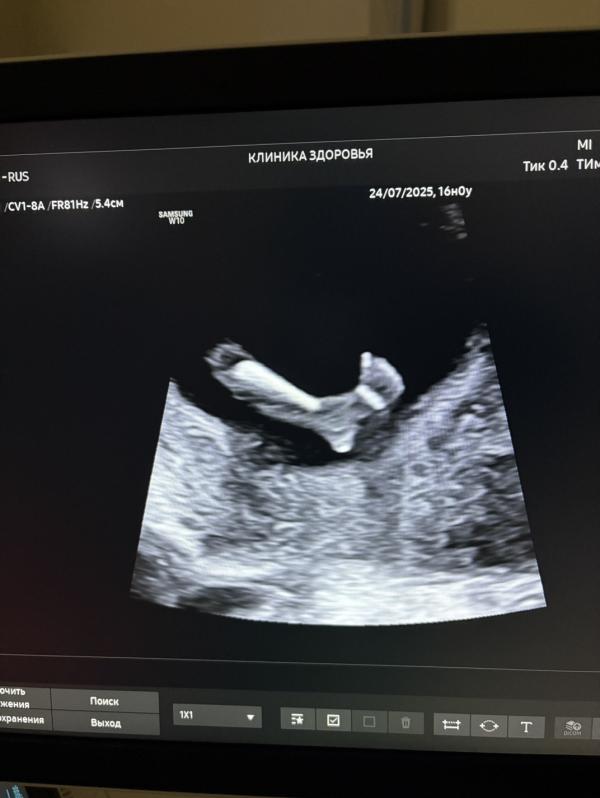

В заключении: двусторонняя эквиноварусная деформация стоп (двусторонняя косолапость). Всё остальное сказала в норме.

Сегодня срок 14.2. Ранее была на 1 скрининге от ЖК в 12.1 и в 12.5 на узи в частной клинике.

Справцева сказала, что по этому снимку всё понятно и деформация сильная.